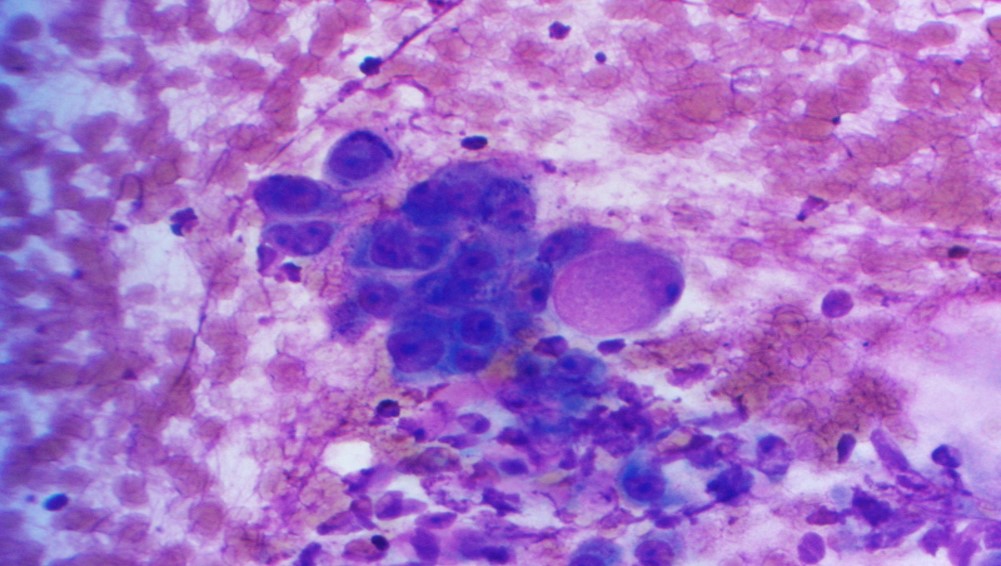

The specimen is cellular and consists of clusters and sheets of large atypical cells with macronucleoli and moderate amounts of somewhat dense cytoplasm. Occasional cells appear to have intracellular mucin and represent muciphages. Scattered benign ductal cells and acini are noted. Necrosis is absent. These findings are consistent with a high-grade salivary gland neoplasm, and a high-grade mucoepidermoid carcinoma is favored on cytology. Subsequent resection confirmed the cytomorphologic impression and showed also perineural invasion.

Mucoepidermoid carcinoma is the most common salivary gland malignancy in children and adults, and the most common malignancy of major and minor salivary glands. Low-grade tumors are more commonly cystic, while high-grade tumors are solid and infiltrative. The diagnostic feature is the combination of mucous cells, epidermoid/squamoid cells, and intermediate cells (which resemble squamous metaplastic cells). High-grade mucoepidermoid carcinomas have a greater proportion of squamoid cells with more cytologic atypia.